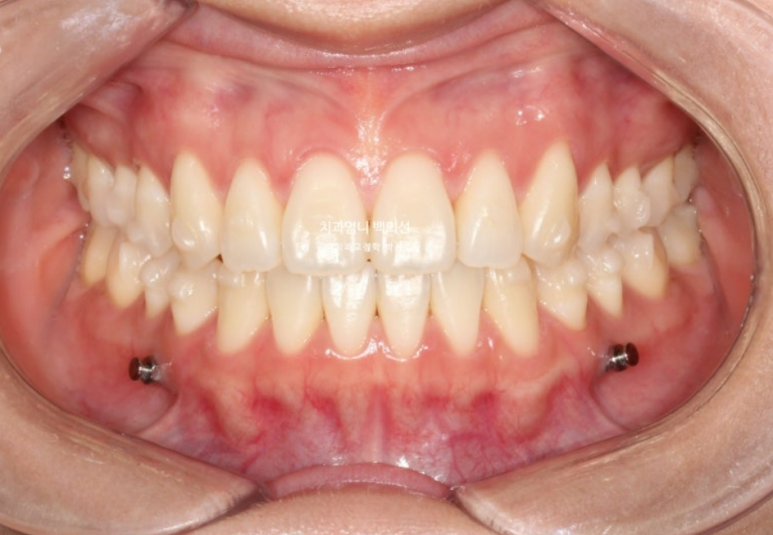

23년 12월 1번장치를 끼기 시작해서 25년 1월까지 총 51개 장치를 다 낀 후 모습입니다.

25.01

앞니 개방교합은 해소가 되었지만 앞니 중심선 불일치가 약 1mm 남았습니다.

우측 어금니 교합은 약간 떠있는 상태이고

좌측 어금니 교합은 좋습니다.

배열도 좋습니다.

교정용 나사는 위 2개 아래 2개 총 4개를 식립해서 진행했습니다.

첫번째 세트 51개 장치 안에서 미니스크류를 이용한 상악 어금니 합입과 하악 어금니 후방이동이 잘 일어났습니다.

교합 안정화와 중심선 개선을 목표로 추가장치 제작에 들어갔습니다.